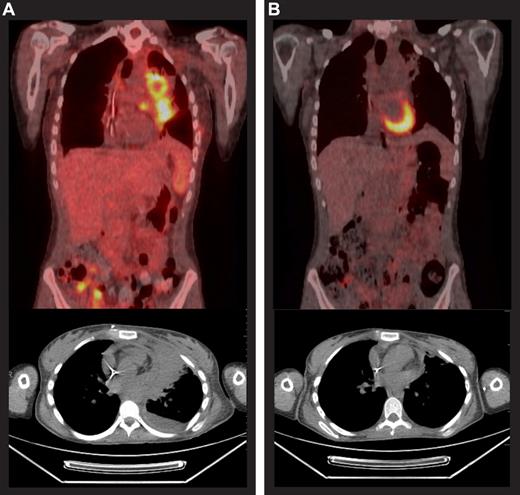

The median PFS for all patients was 7.8 months (range, 0.5-12.2+) and the median overall survival (OS) had not been reached (Figure 1), because 23 patients remained alive at the time of data collection with a median follow up of 34 weeks (range, 2-55). For the 24 patients who were evaluable for response, the median PFS was not reached for patients with CR (n = 9), 34 weeks (range, 20.6-34) for patients with PR (n = 3), and 29 weeks (range, 2.1-44.1) for those who did not have an objective response (n = 12; Figure 2). An example of early response is provided in Figure 3.

Case study before and after brentuximab vedotin therapy. Positron emission tomography scans before (A) and after (B) 9 cycles of brentuximab vedotin for a 20-year-old patient who had been diagnosed with HL 3 years earlier. The patient had received 4 cycles of doxorubicin, bleomycin, vincristine, etoposide, prednisone, and cyclophosphamide followed by external beam radiation that yielded a CR lasting 2 months. She was next treated with 2 cycles of ICE, achieving a PR lasting 1 month. Subsequently, gemcitabine, vinorelbine, and doxorubicin (GND), followed by BEAM autoSCT yielded a PR lasting 3 months. She underwent alloSCT for relapsed disease, conditioned with busulfan, fludarabine, and total body irradiation (200 cGy) and had a matched, unrelated donor, but experienced disease progression 4 months after alloSCT. She received her first dose of brentuximab vedotin in December 2009, achieved a PR before the third dose, and a CR was reported after the ninth dose. She completed 16 treatment cycles and remained in CR at the last contact, 6 months after the last dose of brentuximab vedotin.